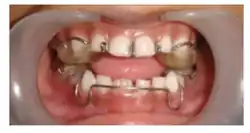

Figure 5: Image depicting a with acrylic capping of lower incisors[10]

Lower incisor capping in a Twin Block appliance is a modification introduced to help control the forward tipping (proclination) of the lower incisors during functional therapy. Initially, it was believed that adding acrylic capping as seen in Figure 12, over the lower incisors could prevent this movement. However, studies have shown that even without capping, a slight 5-degree proclination may occur during the active treatment phase, but the incisors tend to return to an upright position during the support phase. Additionally, research indicates that acrylic capping does not provide a significant restraining effect on incisor inclination. Instead, proclination is primarily influenced by the lingual pressure of the appliance components as the mandible naturally rebounds to its resting position. Another drawback of incisor capping is the potential for decalcification at the tips of the lower incisors, raising concerns about enamel health. Given these findings, the effectiveness of lower incisor capping in preventing proclination remains questionable, and its clinical benefits should be carefully weighed against potential risks.[10]